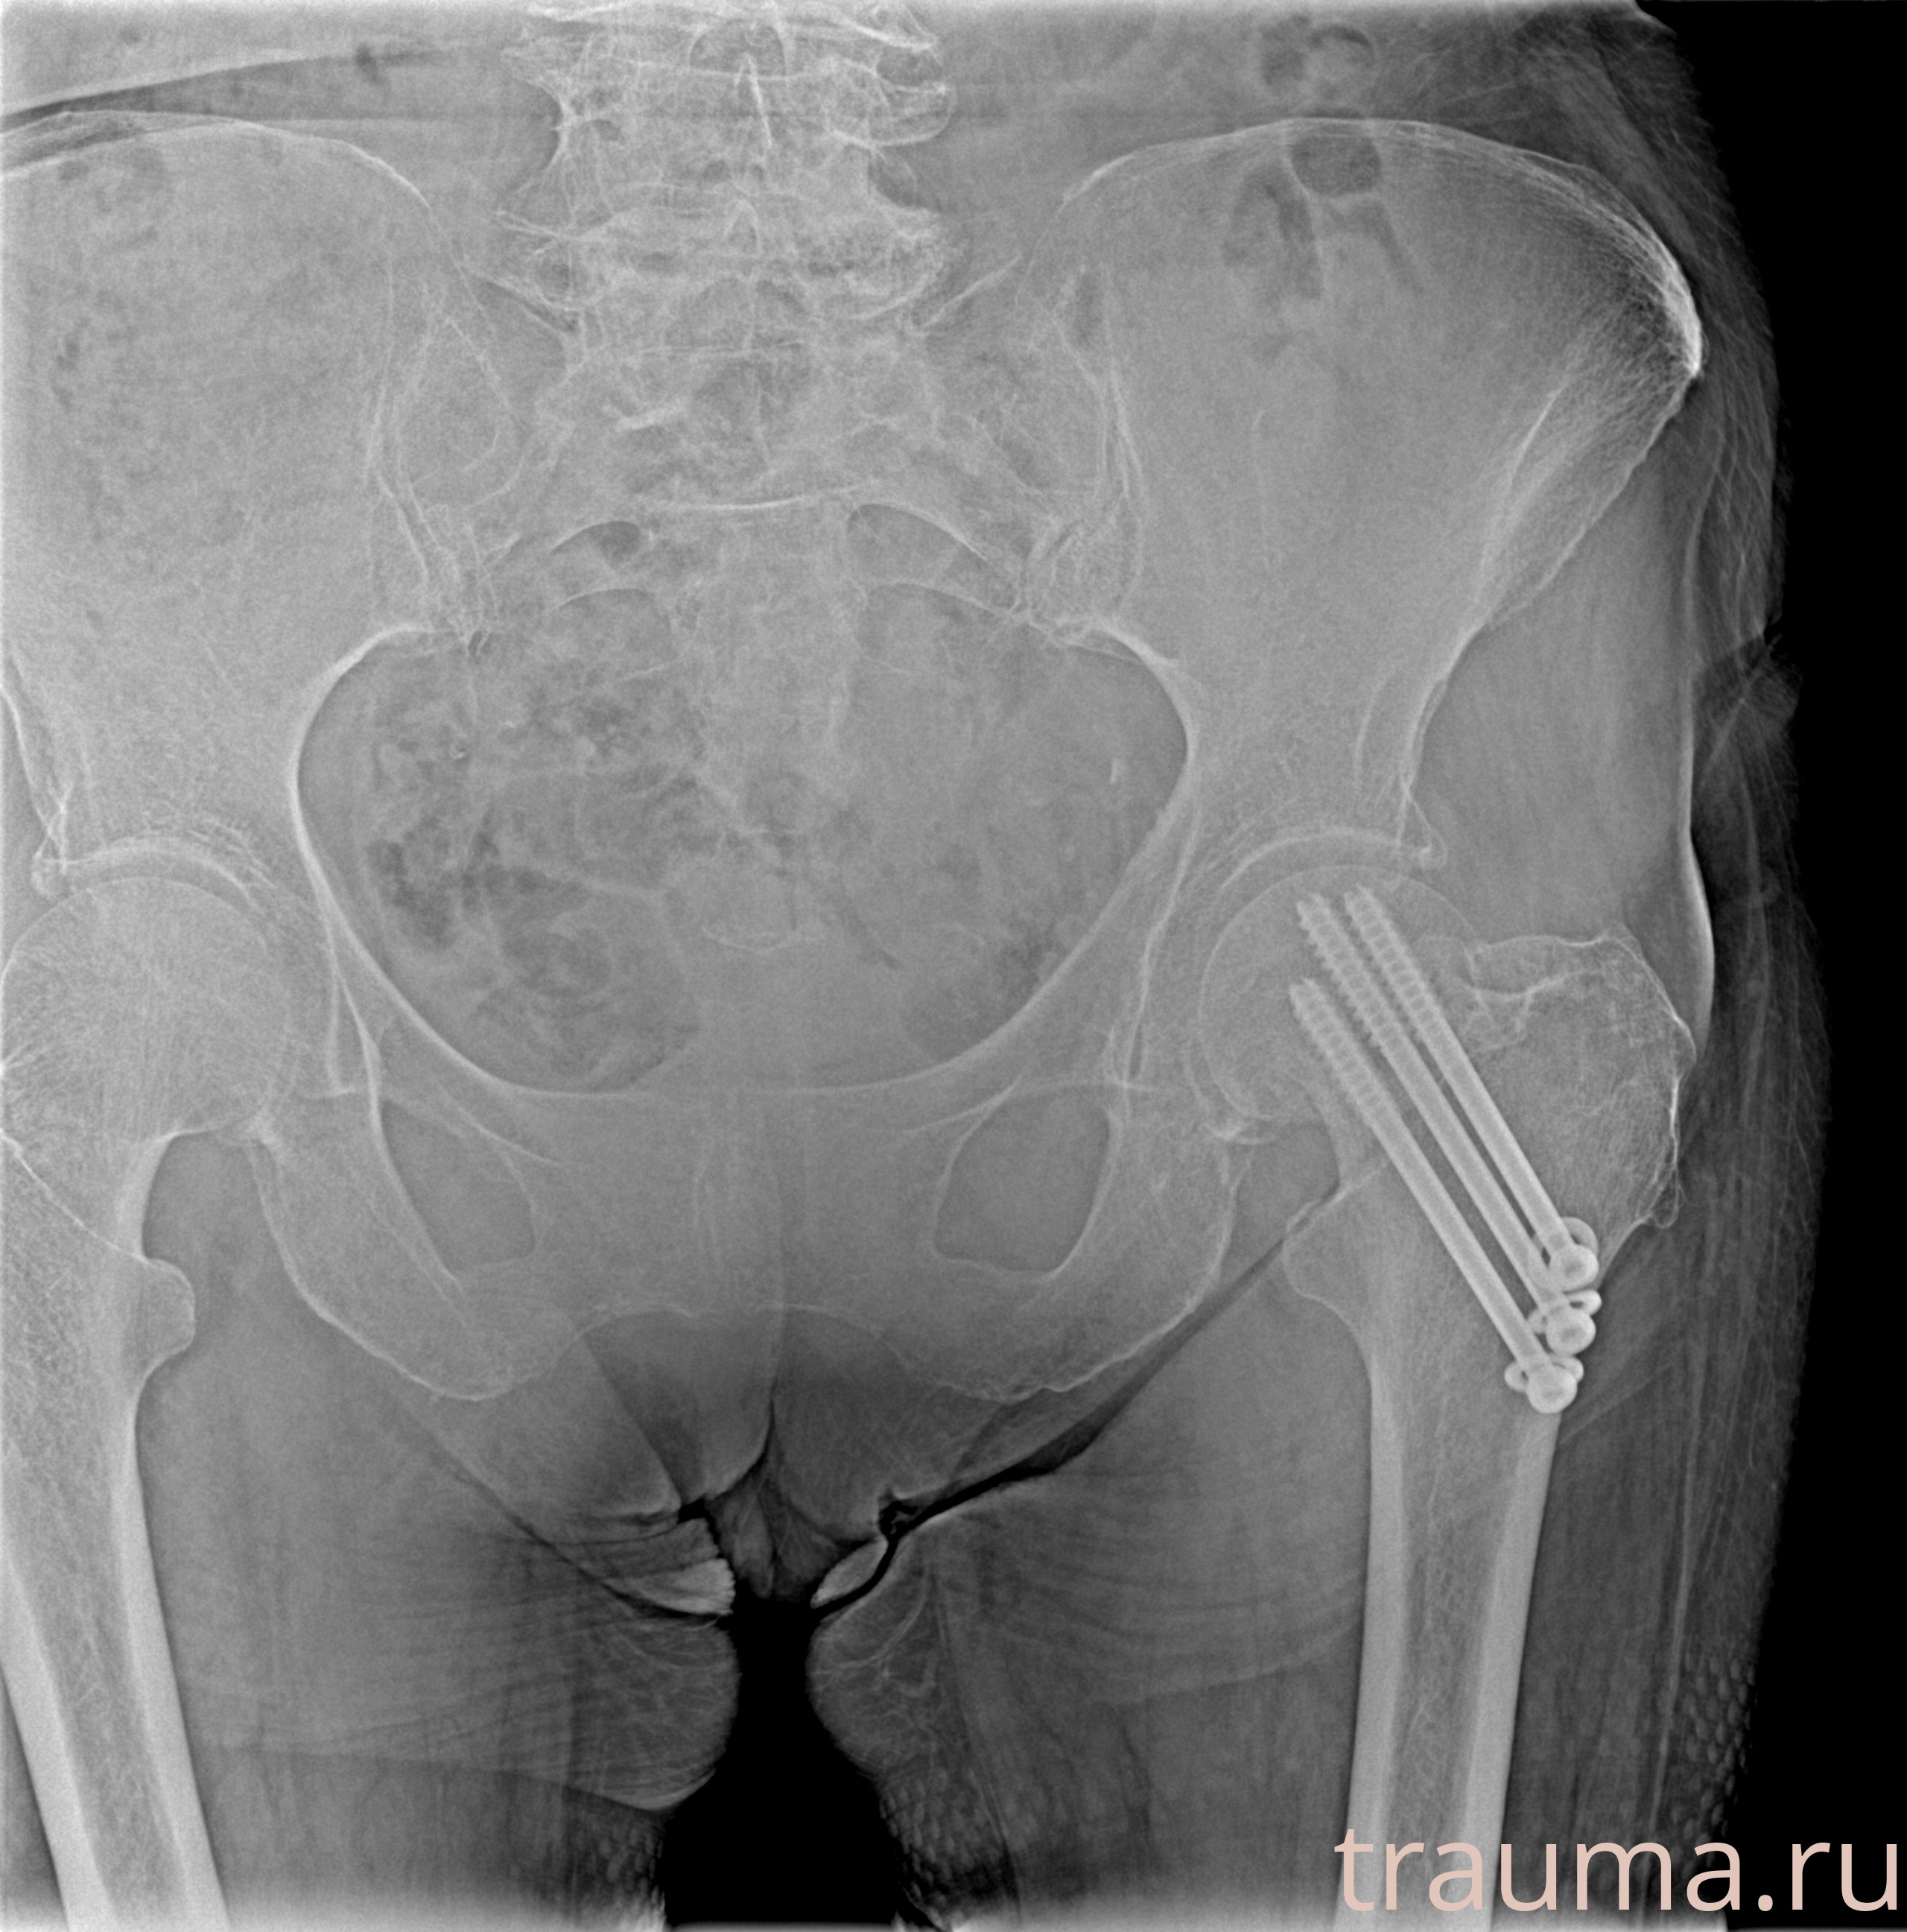

Рентген на дому: по вашему адресу приезжает врач-рентгенолог, травматолог-ортопед с мобильным рентгеновским аппаратом, проводит диагностику травмы или заболевания, делает необходимые рентгенограммы, дает рекомендации по дальнейшему лечению. Получить качественные снимки в домашних условиях возможно благодаря уникальной методике, разработанной МосРентген Центром для института  Склифосовского